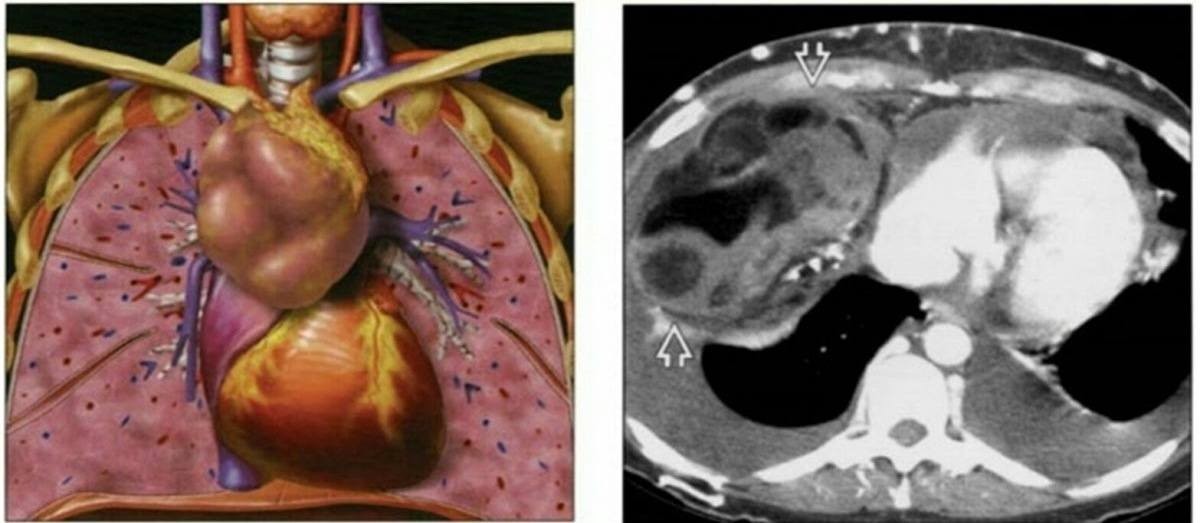

TS.BS. Ngô Gia Khánh: U/ Nang trung thất là những khối u nguyên phát trong khoang trung thất – khoảng không gian bên trong lồng ngực nằm xen giữa tim và hai lá phổi. U/ nang trung thất có nhiều loại, có thể lành tính hoặc ác tính, tùy vào vị trí người ta chia ra u trung thất trước, u trung thất trên, u trung thất giữa, u trung thất sau hoặc gọi tên cụ thể theo nguồn gốc khối u như: u tuyến ức, u nang màng tim, u thần kinh trung thất sau…